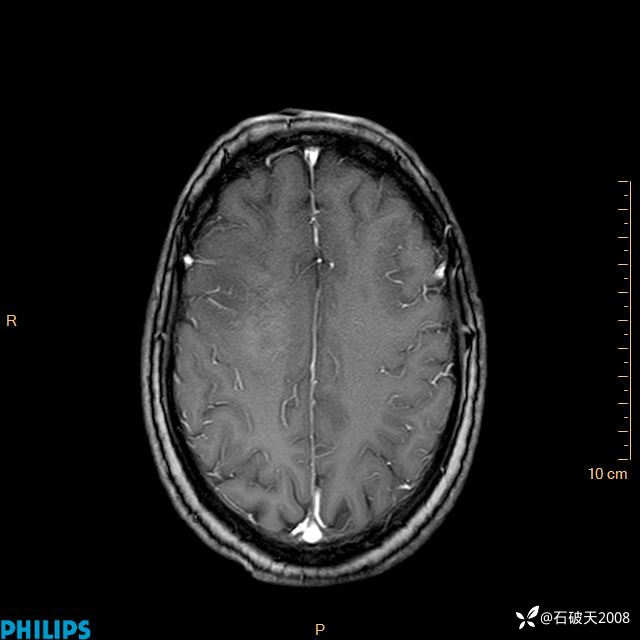

2020.11.14MR

增强轴位